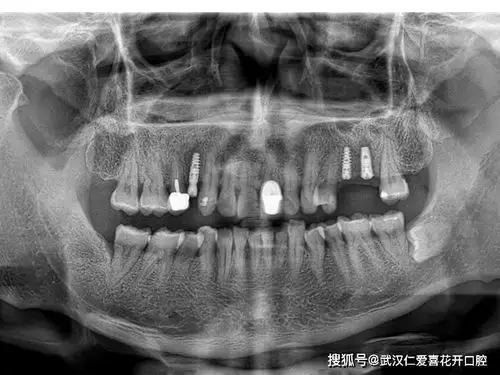

种牙牙片欣赏

我的种植牙日记机械维修工程师的渡江口腔种植修复之路